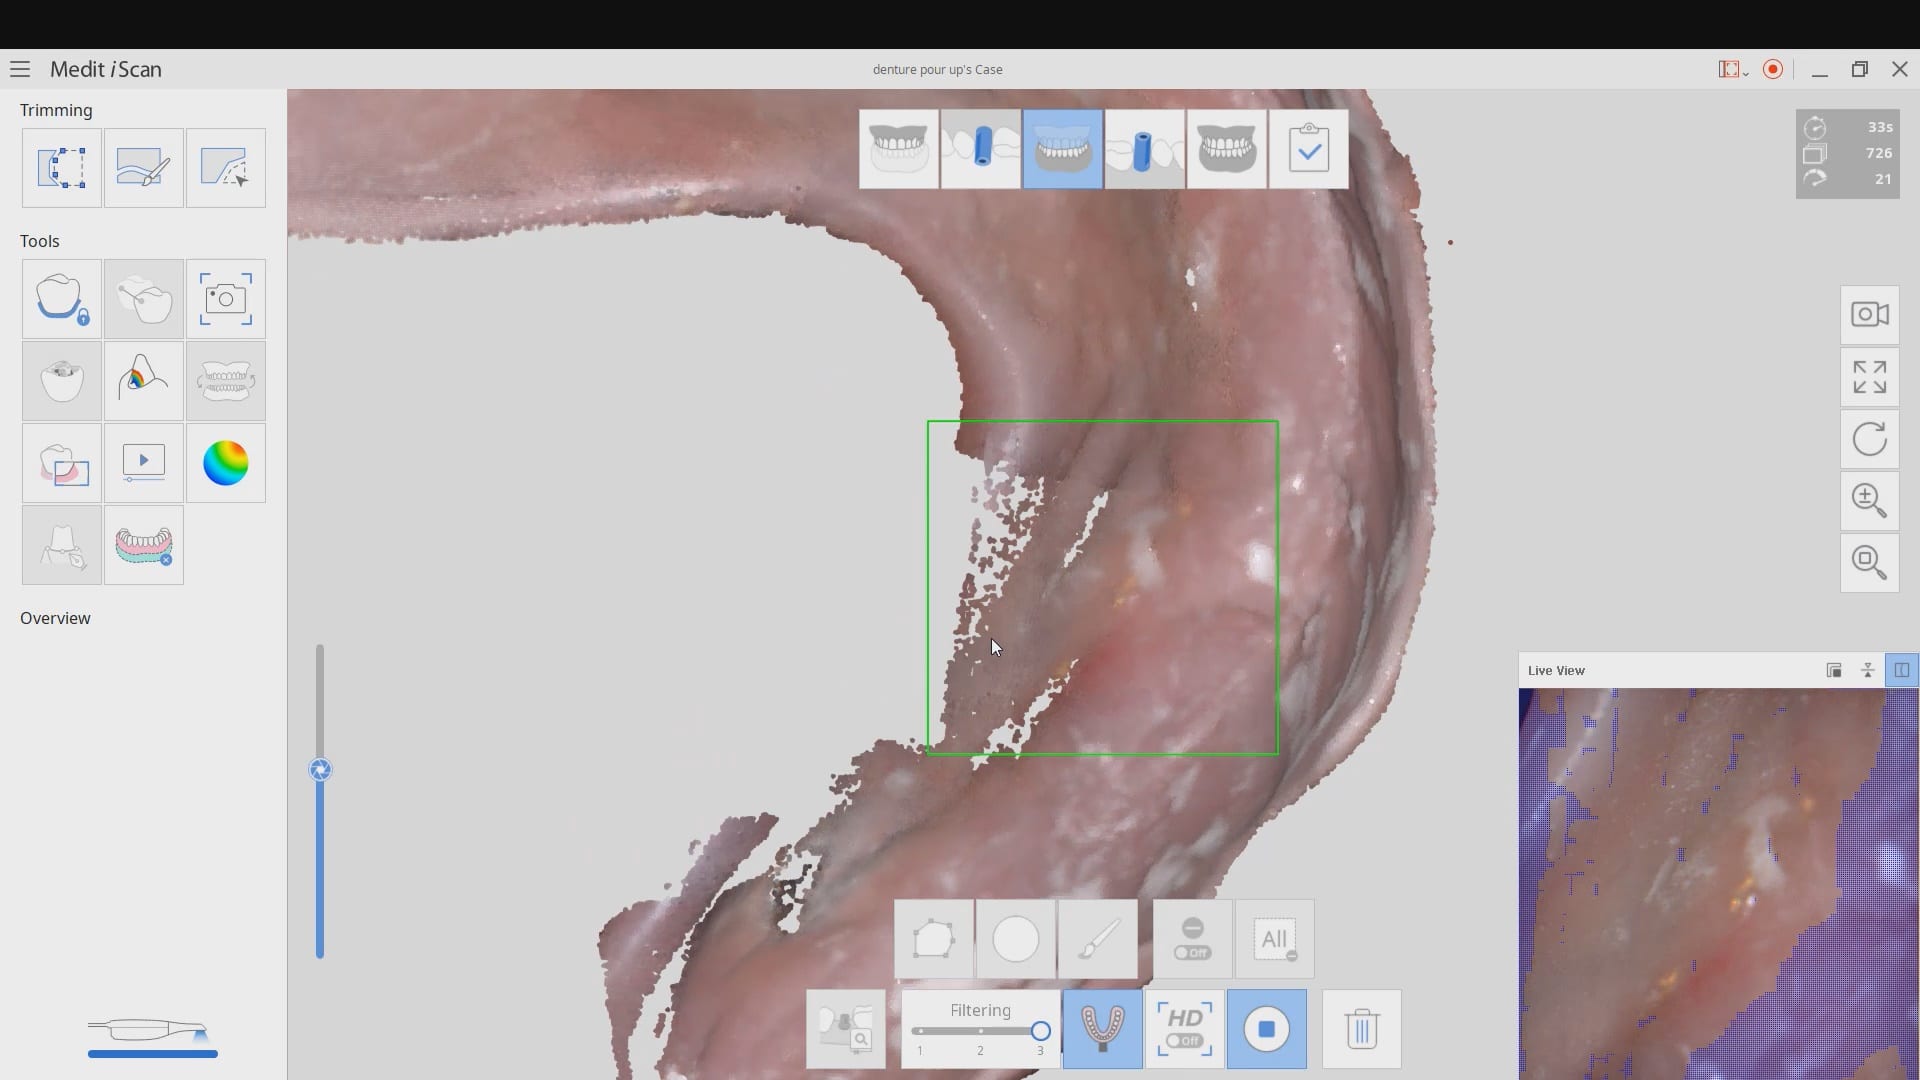

November 19, 2019Have you ever compared the milled product with the designed restoration? We scanned with the medit i500, designed with exocad and milled with coritec. after try-in, we scanned the restoration […]